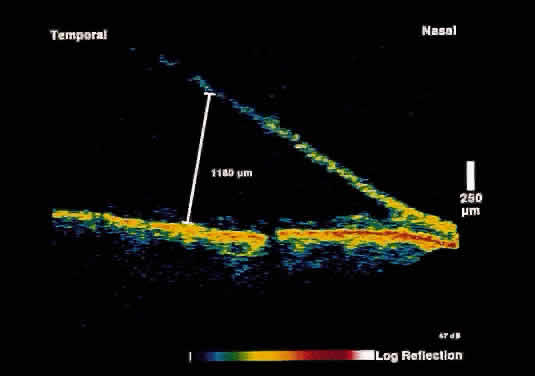

Fig. 3. Several weeks later, an OCT taken through the same area reveals partial

resolution of the neurosensory detachment. Fig. 3. Several weeks later, an OCT taken through the same area reveals partial

resolution of the neurosensory detachment.